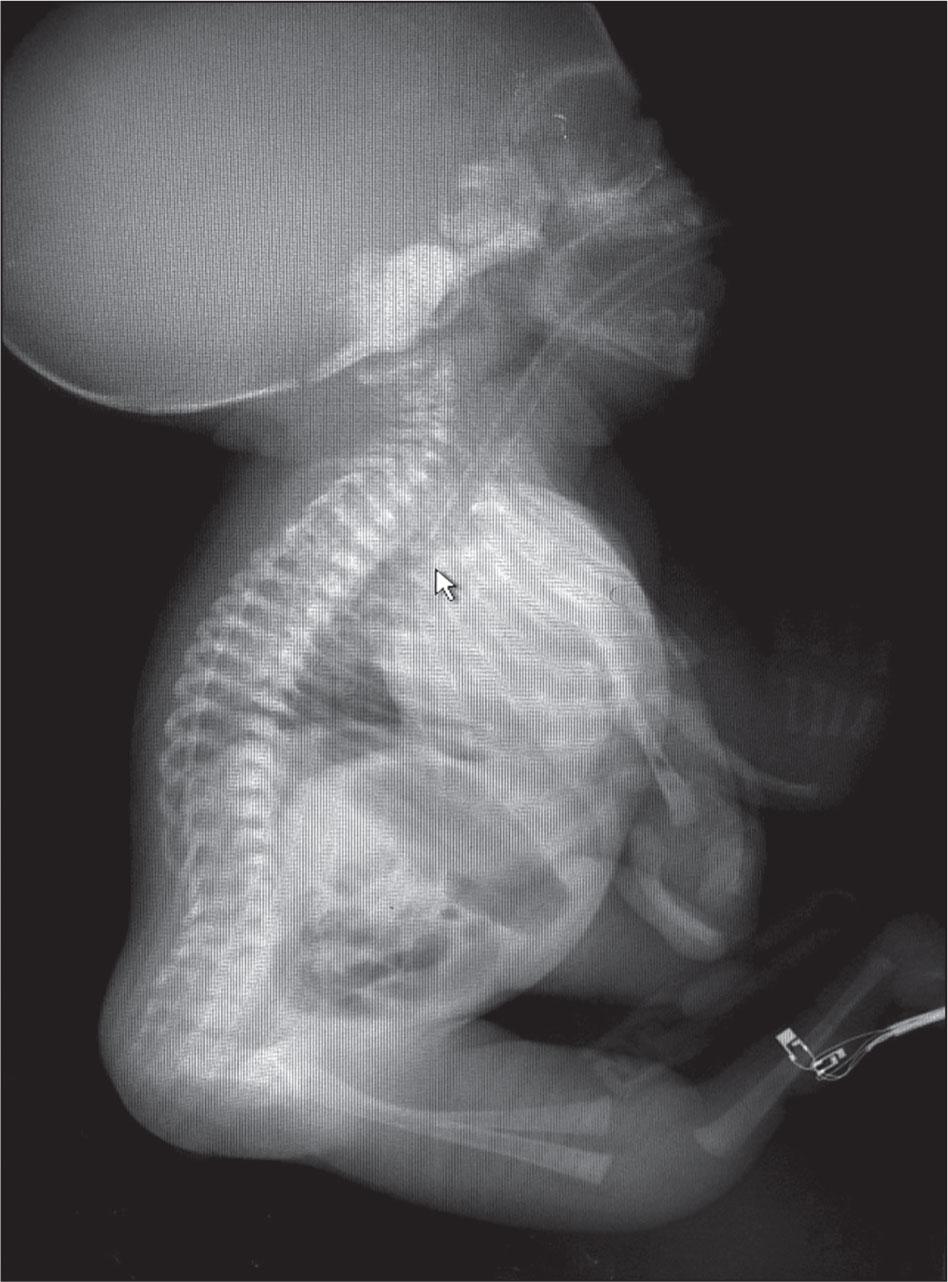

Whole-body X-ray of the patient.